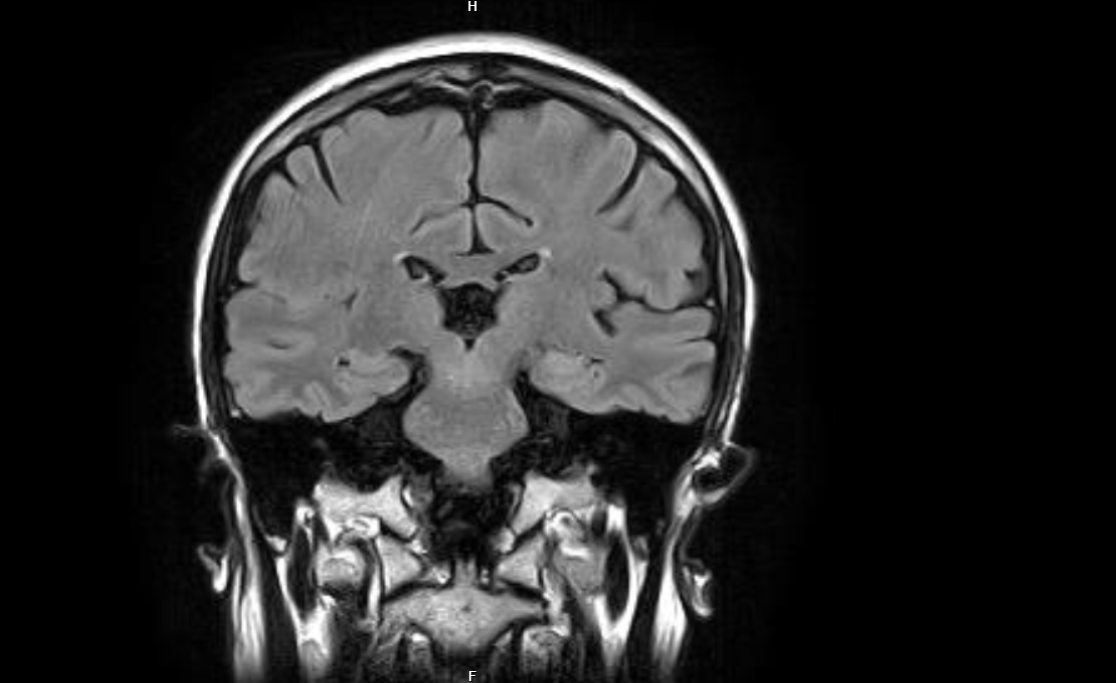

A fag told me the other day that you can just burr the bone of the braincase, and this is truly stupid and demented because look at how thin the bone is. This is an MRI sagittal slice of a tranny. The bone is super thin. If the bone were thick, it would be easy to fix it. You would burr it and call it a day. The problem is that the bone is super thin but it's just the shape and the expansion that are different.

The MRI is to show how thin the bone is. Are you stupid? Look at how thin the bone is and tell me if you can make it thinner. It wouldn't change the brain matter.

That is a frontal slice not sagittal.

That's a coronal slice, not a sagittal